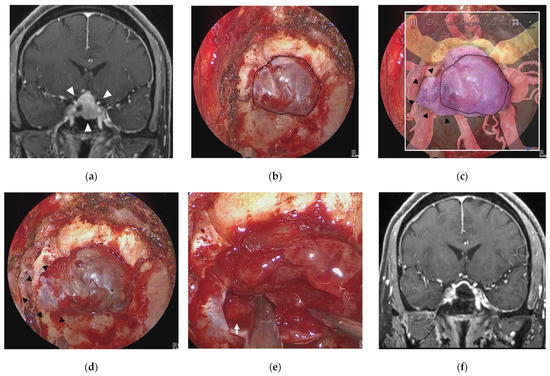

3.3. Illustrative Case 3 (Case 10)